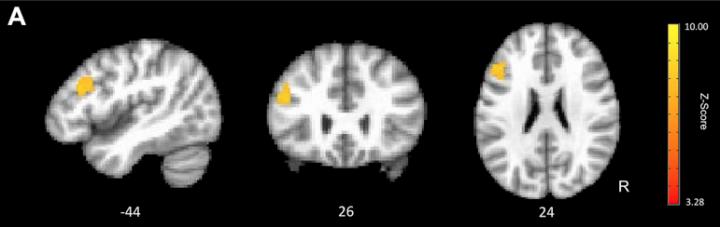

Using functional magnetic resonance imaging (fMRI), an imaging technique that measures brain activity, researchers examined all three groups at the beginning (baseline), middle, and end of the study while participants performed computer-based speed tasks in the scanner.

The fMRI results provided evidence that cognitive training improved speed-related neural activity. While all groups showed faster reaction times across sessions, the cognitive training group showed a significant increase in the association between reaction time and frontal lobe activity. After training, faster reaction times were associated with lower frontal lobe activity, which is consistent with the more energy-efficient neural activity found in younger adults.

In contrast to the cognitive training group, the wait-listed and physical exercise groups showed significant decreases across sessions in the association between reaction time and frontal lobe activation.